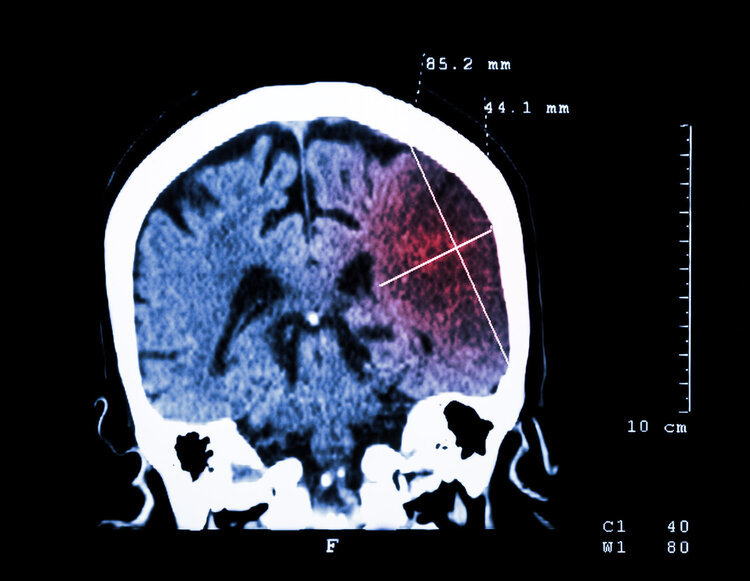

脑梗死又称缺血性脑卒中,是一种由于脑动脉粥样硬化,血管内膜损伤,引起脑动脉管腔狭窄。又因多种因素使局部血栓形成,导致动脉狭窄加重或完全闭塞,最终造成脑组织缺血、缺氧、坏死的一种脑血管病。

脑梗是一种患病率非常高的疾病,据《柳叶刀》披露的最新数据显示:全球新发脑梗塞1370万人,中国新发脑梗塞551万人,中国的脑梗塞人数占全球总人数的40%。